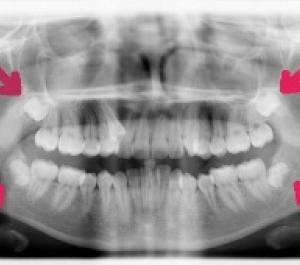

X-ray of teeth showing wisdom teeth needed to be extracted

Again at Capital Dental we pride ourselves as General Dentists to handle most surgical procedures including the removal of one to many teeth including wisdom teeth extractions in our office. We will be sure that you are completely comfortable, if sedation is necessary.